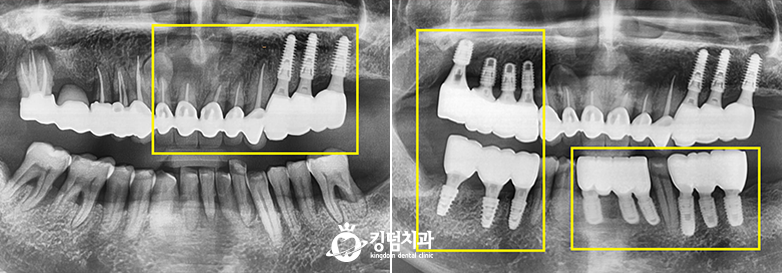

• 킹덤치과 전후사진

• 잇몸뼈 녹음, 2차 충치

• Before After

• 압도적인 실력과 신뢰의 차이

• 본 컬럼은 56조 제 1항의 의료법을 준수하여 작성되었으며 실제 내원 환자분의 동의하에 공개된 치료과정의 사진이 포함되어 있습니다.

개인에 따라 진료 및 치료방법이 다르게 적용될 수 있으며, 효과와 부작용이 다르게 나타날수 있는점을 안내 드립니다.